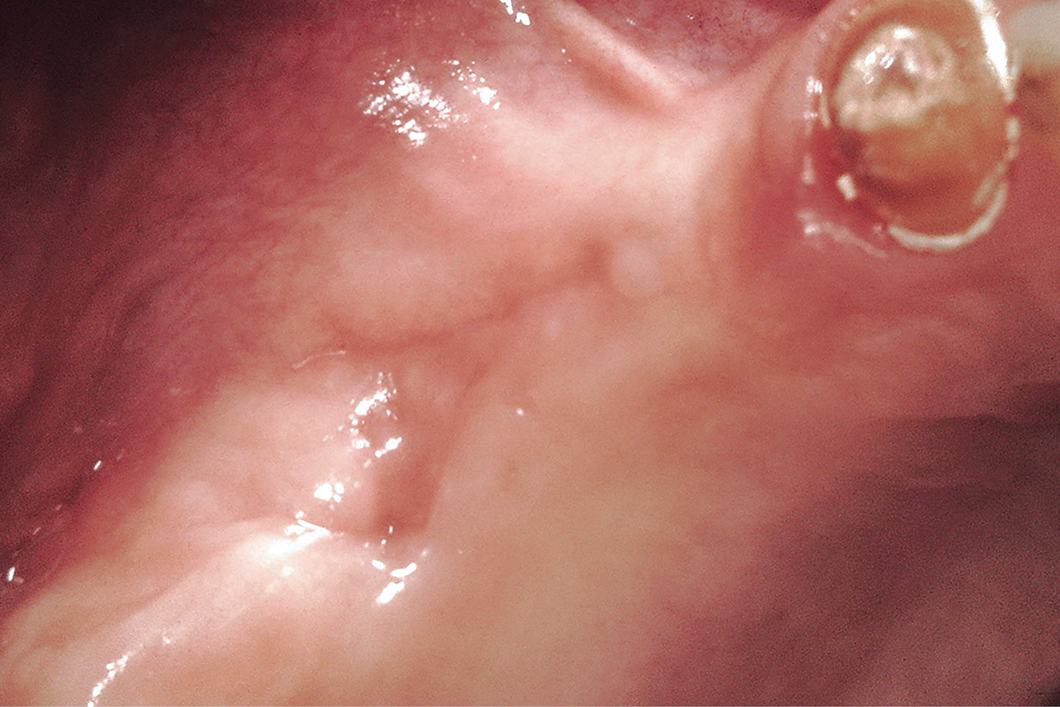

Im Bereich des anterioren Oberkieferswurde eine pneumatisierte Sinushöhlefestgestellt.

Aufgrund des atrophierten Alveolarkamms war es nicht möglich, das Implantat in einer korrekten Position zu setzen, um eine angemessene ästhetische Rehabilitation zu erreichen.

Eine laterale Sinusboden-Elevation mit Geistlich Bio‑Oss® wurde im Bereich des rechten Eckzahns/Prämolaren durchgeführt. In diesem Fall ermöglicht der laterale Fensteransatz eine bessere Blutversorgung in der rekonstruierten Region.

Nach der Sinusboden-Elevation wurde eine Rekonstruktion des Alveolarkamms mit 3-D-Technik nach F. Khoury durchgeführt. Der Knochenblock wurde aus dem Ramus entnommen. Nach der Präparation der beiden Knochenblöcke wurde jeder mit einer Schraube in der oberen Frontzahnregion fixiert. Die restlichen Hohlräume zwischen den Blöcken und darum herum wurden mit einer Mischung aus Geistlich Bio‑Oss®Partikeln und autogenen Knochenchips gefüllt.